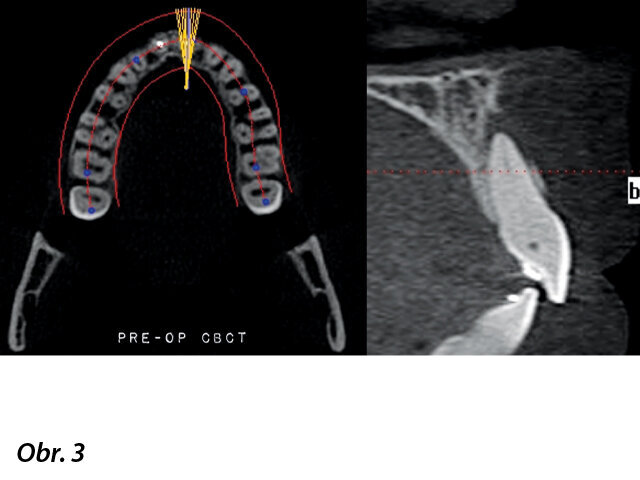

Pacientka, 22 let, byla do privátní kliniky odeslána s bolestí v horního levého středního řezáku v anamnéze. O 9 let dříve prodělala pacientka zubní trauma. Zub byl zbarven dožluta a reagoval citlivě na poklep (obr. 1). Testy vitality chladem a elekrotesterem byly negativní. Radiologické vyšetření ukázalo značně kalcifikovaný kořenový kanálek (obr. 2). Přítomnost radiolucence odpovídající apikální periodontitis byla potvrzena CBCT skenem (i-CAT, Imaging Sciences International) (obr. 3).

Prostor kořenového kanálku bylo možno pomocí původního radiologického a 3D zobrazení identifikovat v apikální třetině. Na základě výsledků klinických a radiologických vyšetření byla stanovena diagnóza nekrotické pulpy se symptomatickou apikální periodontitis a bylo doporučeno ošetření kořenového kanálku. Po analýze a diskuzi s pacientkou byla zvolena navigovaná endodoncie jako nejvhodnější terapeutický postup.